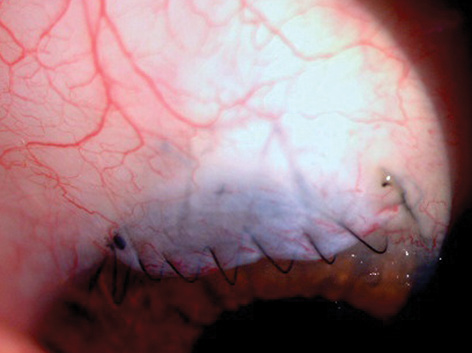

- closure, such as placing sutures of precise tension to approximate a scleral flap or ensuring a watertight conjunctival closure (Figures 1 and 2)

Figure 2. Running closure with nonabsorbable suture material on a taper point needle.